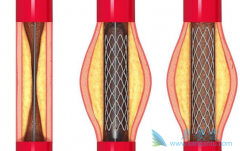

为了改善冠心病介入治疗短期和长期的疗效与安全性,所以研发了支架。第一代支架是金属裸支架,使冠心病介入治疗前进了一大步,使介入治疗变得非常安全,当血管发生严重狭窄时单纯球囊扩张预处理后,再用支架把血管完全撑开,就能解除心肌缺血危险,而且 ...

心脏支架手术 ,又被称之为冠状动脉支架植入手术,目前是冠心病的最重要治疗方式之一,手术期间需要在患者的冠状动脉处放置支架以拓宽狭窄的血管壁,使冠状动脉复通并使血液正常的流动,目前在三种情况下建议尽快进行心脏支架手术。情况一:患者的血管 ...

不少人都听过心脏支架手术,这种手术堪称是当代心脏病学最伟大的一项发明。你知道这个小小的支架是怎么放到心脏里去的吗? 心脏支架 是通过介入手术的方式植入到人体的,我们可以从心脏介入手术可是说起,这样更好理解。心脏介入原理其实并不复杂。 ...

心脏支架 选哪种?放最好的支架?还是放最贵的支架?今天就给大家答疑解惑!心脏支架由具有强支撑力的合金制成,不同厂家支架的金属结构略有差别。心脏支架没有植入体内之前,包裹在球囊外面。植入时给球囊加压,支架打开至预定直径,使支架与血管壁完 ...